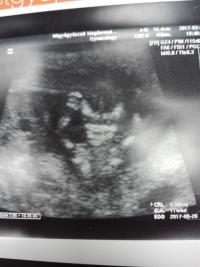

Minden okè,55mm-es a kis drágám, tarkóredő 0.7mm,orrcsont rendben,kezecskèk,lábacskák megvannak. Az integrált tesztet megcsináltatjuk,ahhoz le is vette a vèrt, 4 hèt múlva meg a második vèrvètel. Legközelebb jó sokára, a 19. hèten kell mennem uh-ra.

Valamiért elfordítódik az a kép, ahogy feltöltöm. De mindjárt megpróbálom újra :) Azon közelebbről van a kis drágám, a karjai a feje mellett, felemelve, úgy aludt :)

Vagy fèl órán keresztül ultrahangozott a doki,mert èpp szundizott a drágám,nem nagyon akart felkelni. Aztán már mondta,hogy köhögjek,vagy vmit csináljak,hogy felèbredjen. Az segített is,utána már mocorgott azèrt. :-)